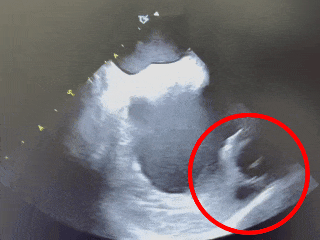

术中DSA肝位造影:双分叶鸡翅型左心耳

肝位造影,心房侧显影,轴向偏前,下缘早分叶

开口23.5mm,深度18.1mm